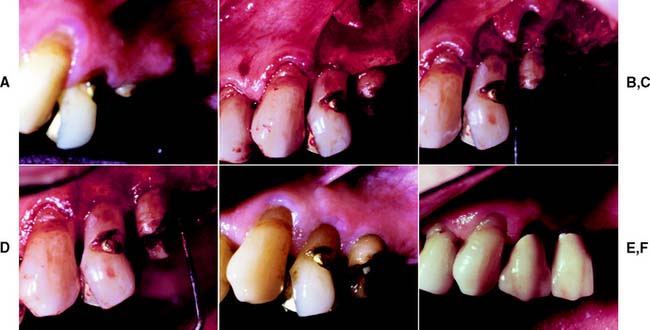

Surgical crown lengthening or extension (Fig. 6-16) may be indicated to improve the appearance of an anterior tooth or when the clinical crown is too short to provide adequate retention without the restoration’s impinging on the normal soft tissue attachment61 or biologic width.* This attachment averages approximately 2 mm in width, and any restoration that impinges on it may cause bone loss because of the effort of the host to maintain the 2 mm distance. If impingement occurs in an interproximal area, it can lead to problems with plaque control and possible osseous resorption.62-64 Therefore, from the standpoint of prognosis, the biologic width should never be compromised.

Fig. 6-16 Surgical crown lengthening. A, Fractured and carious second premolar. B, Reflection of a flap and removal of granulation tissue. C, Bone removed on the mesial aspect to increase the distance to the fracture site to 3.5 mm. D, Distally the bone is removed so that there will be 3.5 mm from the caries to the alveolar crest. E, Healing after the surgical crown lengthening. F, Final crown restoration after cementation, before restoration of the sextant with a removable dental prosthesis.

In some patients, an apparently unsalvageable tooth with extensive subgingival caries, a subgingival fracture, or root perforation resulting from endodontics can be successfully restored after crown lengthening. Crown lengthening increases the crown/root ratio, however, and a pretreatment decision must be made about whether the tooth should be removed or restored.

Crown lengthening may be accomplished either surgically or with combined orthodontic-periodontic65-69 techniques, depending on the patient and the dental situation.

It is sometimes possible to achieve an effective increase in crown length by gingivectomy or removal of gingiva by electrosurgery alone (see Fig. 6-16), although osseous recontouring is most often needed to prevent encroachment of the prosthesis on the biologic width. For these procedures, a full-thickness mucoperiosteal flap is reflected, and the osseous resection creates 3.5 to 4.0 mm of space between the gingival crest and the margin of the existing restoration or carious lesion.61,70 In these instances, however, the following factors should be considered:

Restoration of a tooth that has undergone crown lengthening is commonly undergone in 4 to 6 weeks after the surgical procedure. A clinicale study73 has demonstrated that the biologic width and the position of the free margin of the gingivae exhibited no change at 3 to 6 months after surgery. Therefore, it may be advisable to provisionally restore that tooth in question, either before or immediately after surgical crown lengthening, and subsequently fabricate the final restoration after 3 months.

Although surgical crown lengthening may not be a panacea for fractured, perforated, or badly decayed teeth, it can help solve difficult and/or complex restorative problems when used with proper clinical judgment.